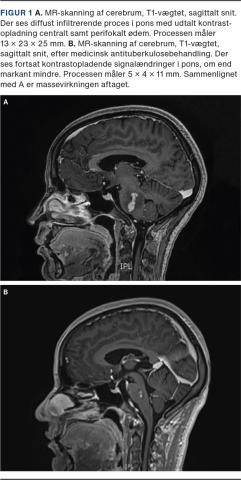

En MR-skanning af hjernen viste en diffust infiltrerende og kontrastopladende proces i pons (Figur 1A) samt to punktate kontrastopladende forandringer i hhv. højre og venstre frontallap. De primære diagnostiske overvejelser var malignitet, herunder astrocytom/gliom og lymfom.

Der blev indledt antituberkuløs behandling med rifampicin, isoniazid, pyrazinamid og ethambutol i initialfasen (to måneder) efterfulgt af kontinuationsfasen med rifampicin og isoniazid (otte måneder) samt prednisolon i fire måneder. Efter endt behandling havde patienten kun let abducensparese. En kontrolskanning 15 måneder efter behandlingsstart viste væsentligt aftagende størrelse af det pontine tuberkulom samt aftagende perifokalt ødem (Figur 1B). De punktate forandringer var ligeledes aftaget i størrelse.